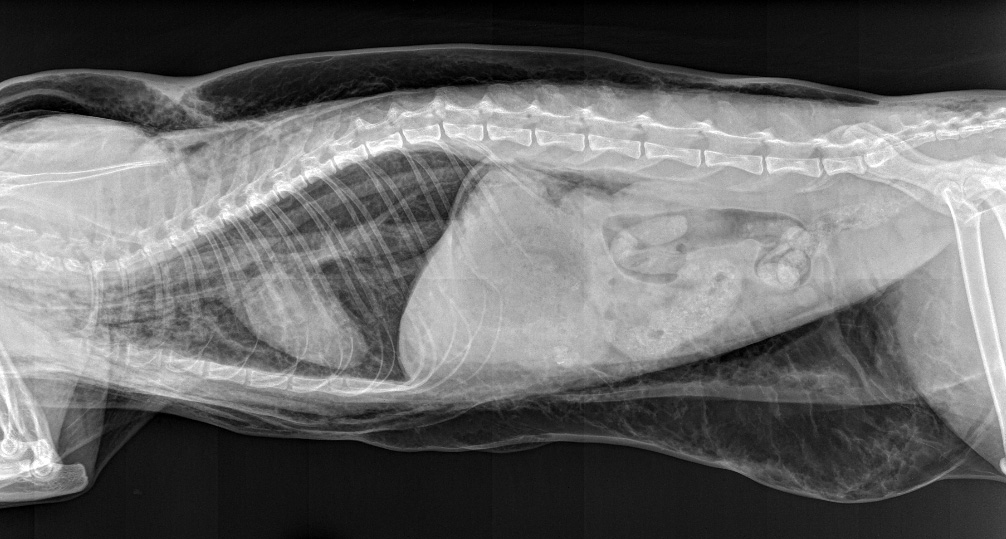

Signalement: Chatte stérilisée de 6 ans.

Histoire clinique: Présentée en dyspnée 12 heures après un détartrage de routine.

Y a t il eu rupture de la trachée lors de l’intubation??

Et bien… la réponse est oui ! (voir le billet sur la suite pour plus d’infos)